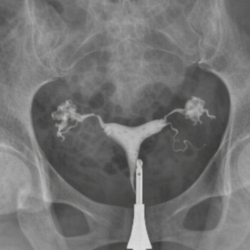

L’ablation complète de l’utérus, appelée médicalement hystérectomie, est l’une des méthodes chirurgicales importantes utilisées dans le traitement des maladies gynécologiques. Cette intervention peut être nécessaire pour diverses raisons telles que des fibromes volumineux, des saignements anormaux incontrôlables, certains cancers gynécologiques, des douleurs chroniques ou un prolapsus utérin avancé.

Aujourd’hui, l’hystérectomie est le plus souvent réalisée par voie laparoscopique. Grâce à cette méthode, l’utérus est retiré à travers de petites incisions sans nécessiter une grande ouverture abdominale. La chirurgie laparoscopique offre des avantages tels que moins de douleur, une durée d’hospitalisation plus courte et une récupération plus rapide.